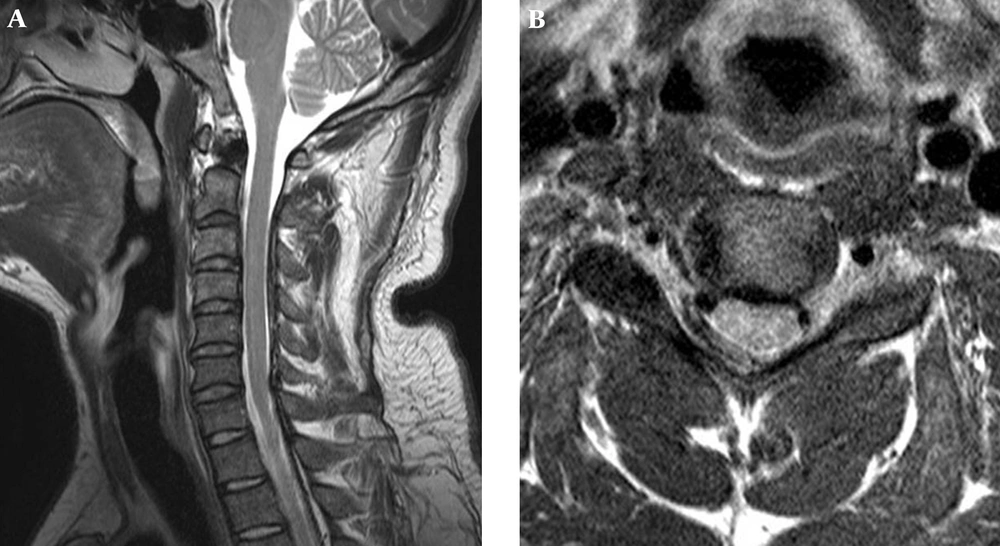

A 28-year-old healthy man developed severe neck and right shoulder pain of a sudden onset while he was getting out of a car. He was admitted to a local hospital where a cervical magnetic resonance imaging (MRI) study was performed. The MRI demonstrated a large epidural mass compressing the spinal cord on the right posterolateral side from C2-C6 (Figure 1). The lesion was isointense to the spinal cord on T1-weighted images, hyperintense on T2-weighted images, and exhibited no contrast enhancement.